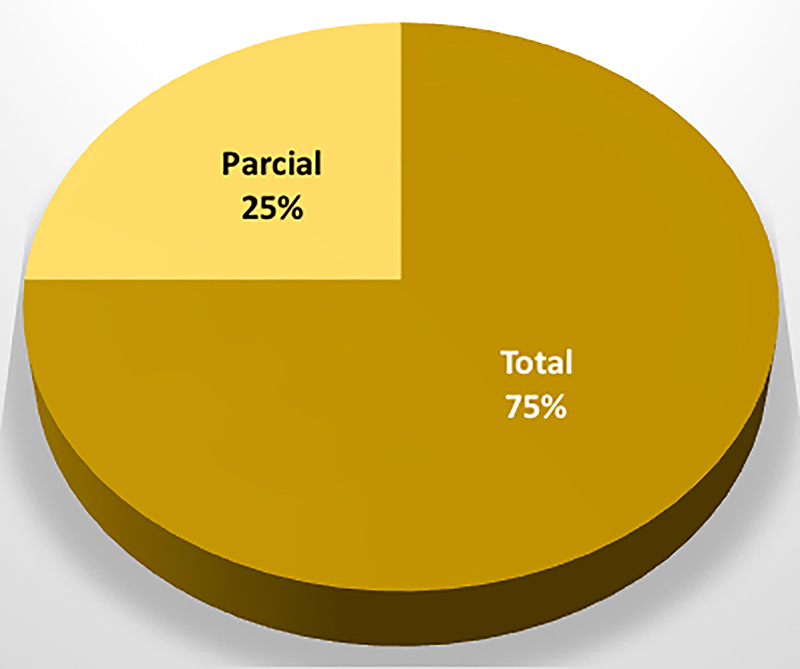

El grado de resección según el hallazgo intraoperatorio y la RM de control fue total en un 75% (n=158) y subtotal en un 25% (n=53). El 60% (n=32) de los enfermos con remanente en RM postoperatoria y/o sin remisión bioquímica fueron clasificados como Knosp grado 3 o 4 en la etapa preoperatoria.

En el grupo de pacientes en los que se objetivó déficit visual preoperatorio (n=88), se evidenció mejoría visual postoperatoria en un 94% de los casos (n=83) (graf. 2). De los 5 casos sin mejoría, 4 permanecieron estables y 1 con deterioro.

Gráfico 2: Seguimiento oftalmológico en los adenomas no funcionantes.